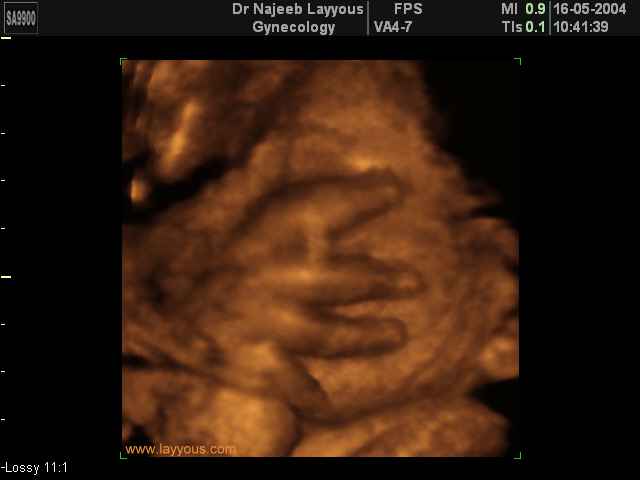

3D Ultrasound Scan Photos of Fetal Limbs | Dr N Layyous

3D Fetal Limbs Ultrasound Scan Photos